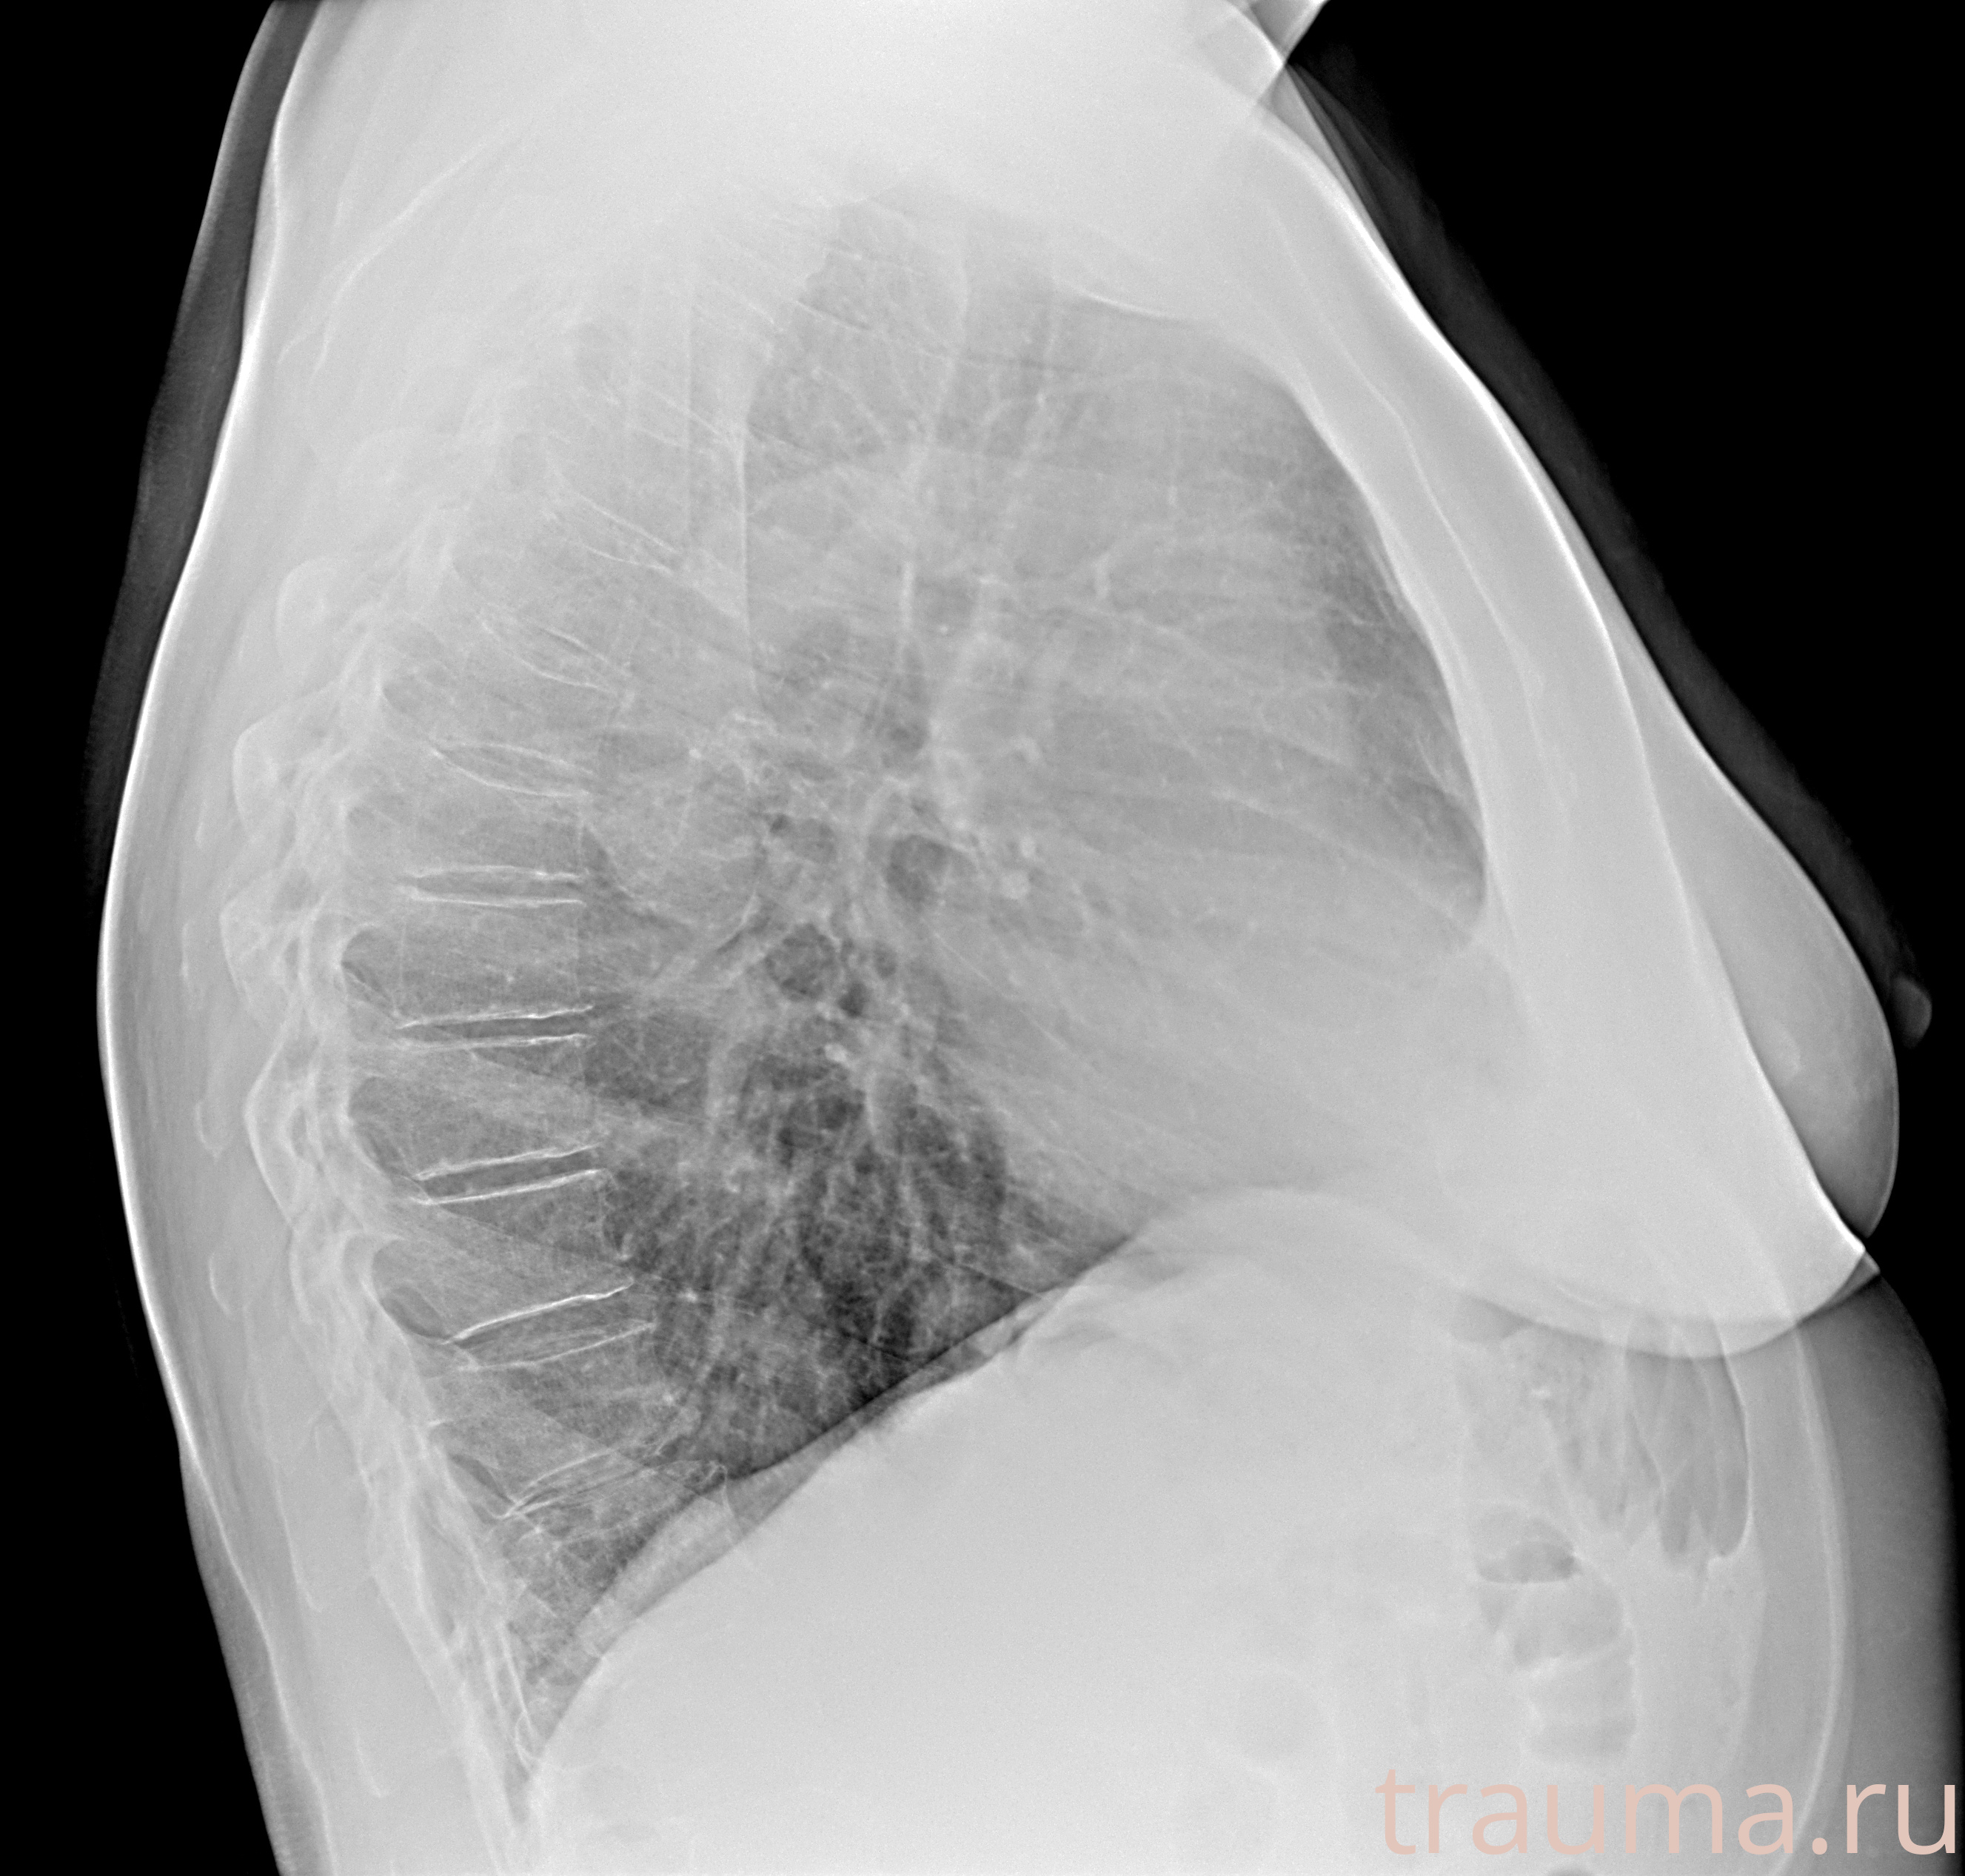

Рентгенограммы

Рентген на дому: по вашему адресу приезжает врач-рентгенолог, травматолог-ортопед с мобильным рентгеновским аппаратом, проводит диагностику травмы или заболевания, делает необходимые рентгенограммы, дает рекомендации по дальнейшему лечению. Получить качественные снимки в домашних условиях возможно благодаря уникальной методике, разработанной МосРентген Центром для института  Склифосовского

Яркость: 1   Контраст: 1   Инвертировать: 0 Увеличение: 1

Перетаскивайте мышь вверх/вниз для контраста, влево/право для яркости. Прокрутка колесом изменяет масштаб. Нажмите Сбросить для возврата к исходному изображению. При увеличении держите мышь в той области, которую хотите рассмотреть.